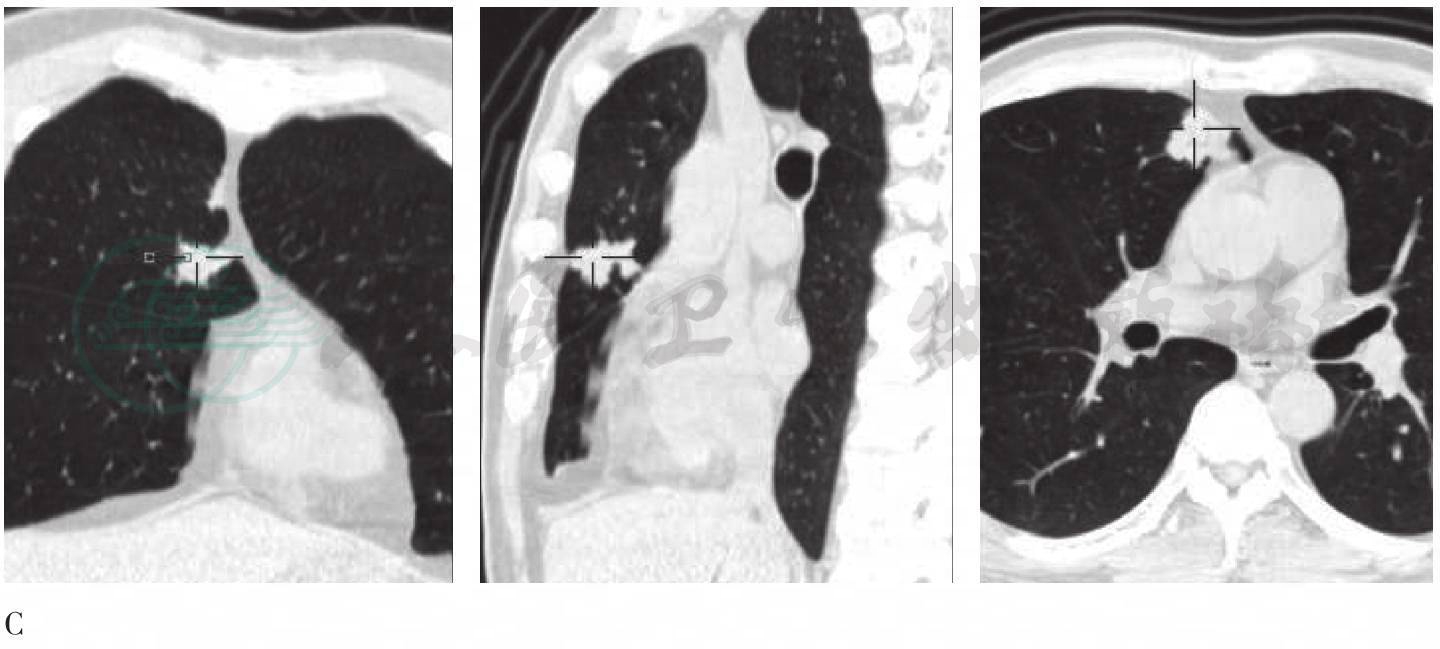

图3 胸部增强CT图

A、B. CT肺窗横断位连续层面;C. CT纵隔窗;D. CT肺窗冠状位、矢状位及横断位。

右肺尖可见极不规则结节(十字交叉),呈瘢痕样改变,中央可见小空洞,周围见磨玻璃密度影

图5 胸部增强CT图

A. CT肺窗横断位层面;B. CT纵隔窗;C. CT肺窗冠状位、矢状位及横断位。

右肺上叶纵隔旁多灶融合结节(十字交叉),约2.6cm,有明显强化